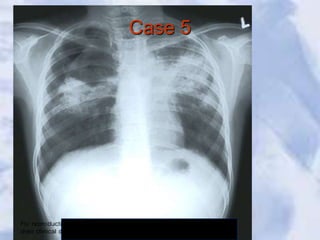

Case 5

Tuberculosis